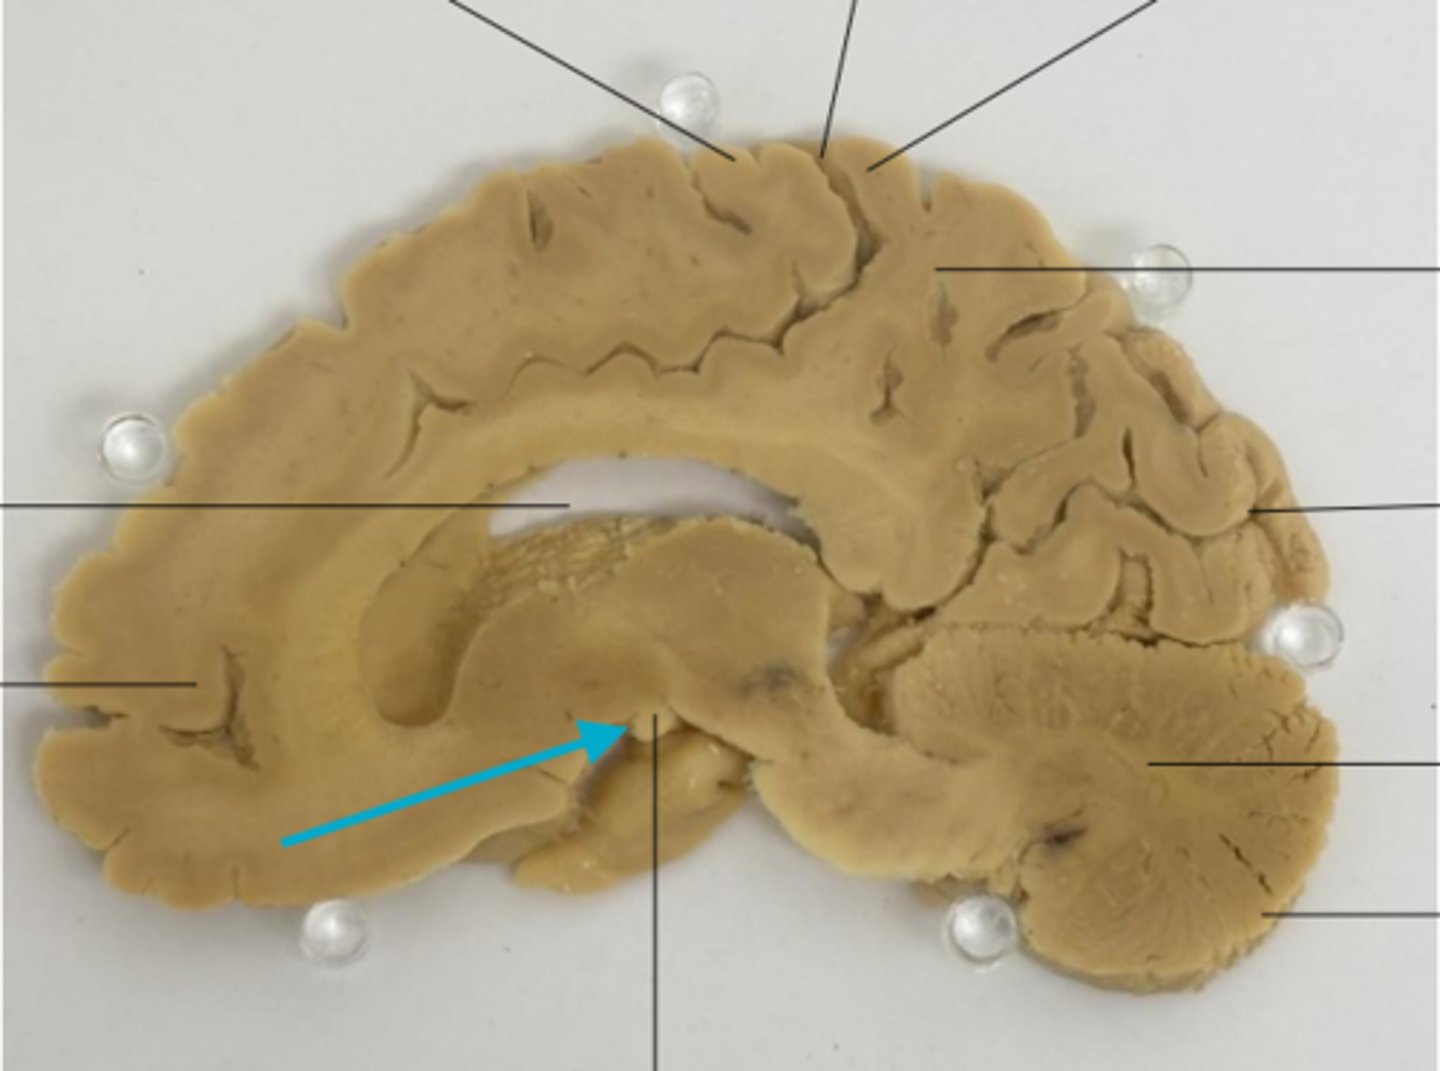

What is the blue arrow pointing at?

What number is the post central gyrus?

what is the blue arrow pointing to?

blue arrow is pointing to which structure?

The area the blue arrow is pointing to?

What area is the blue arrow pointing to?